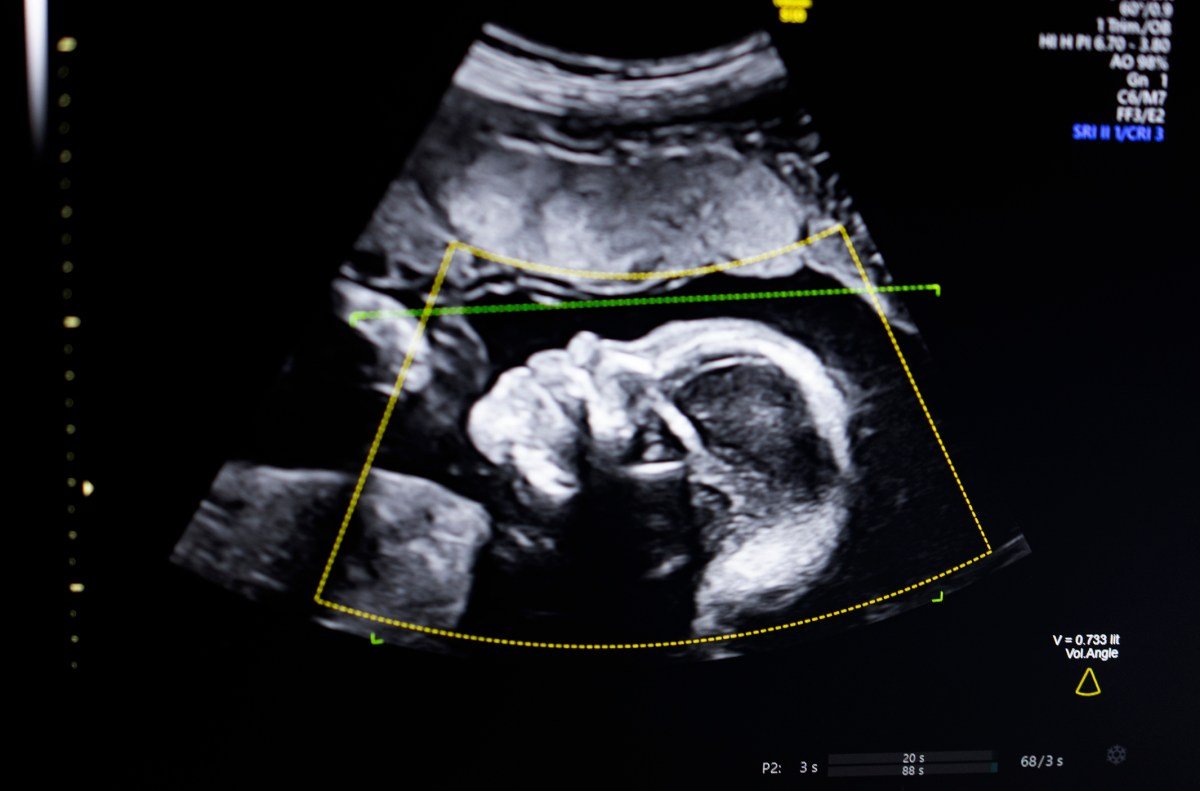

The technology uses computer vision artificial intelligence “to support fetal ultrasound quality assessment, anatomical completeness, automated reporting and seamless integration into clinical workflows,” Bustami told TechCrunch.

Bustami said prenatal ultrasound has become the “cornerstone” of monitoring pregnancies, but low-quality images can lead to misdiagnosis.